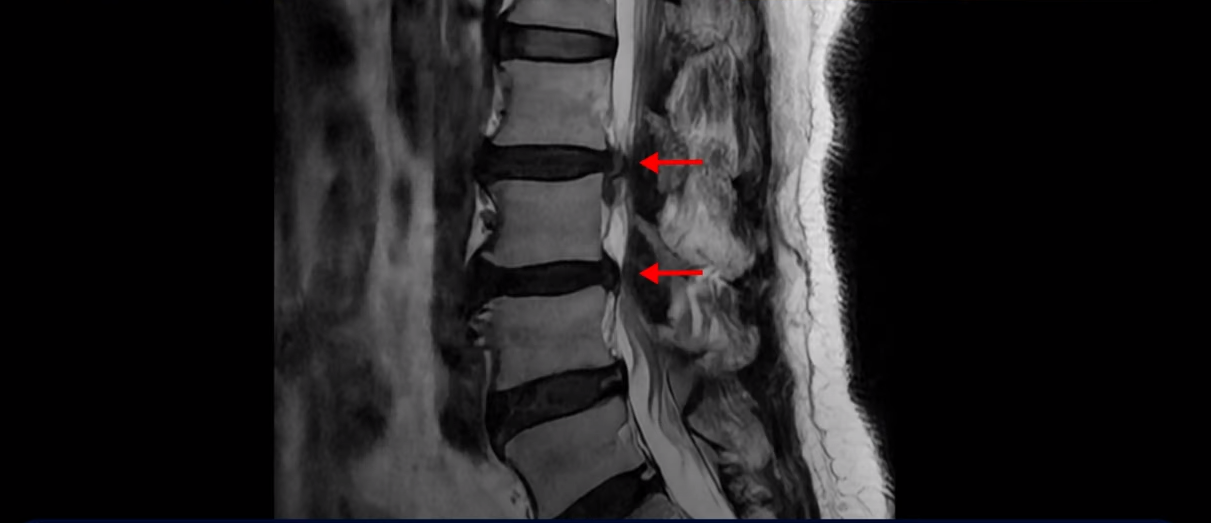

이분 MRI 보시면 2번 3번, 3번 4번이 두 마리가 특히 안 좋습니다.

이 마디는 중심성 협착도 있어서 허리 신경 공간이 많이 좁아져 있습니다.

3번 4번도 중심성 협착으로 신경 공간이 좁아져 있습니다.